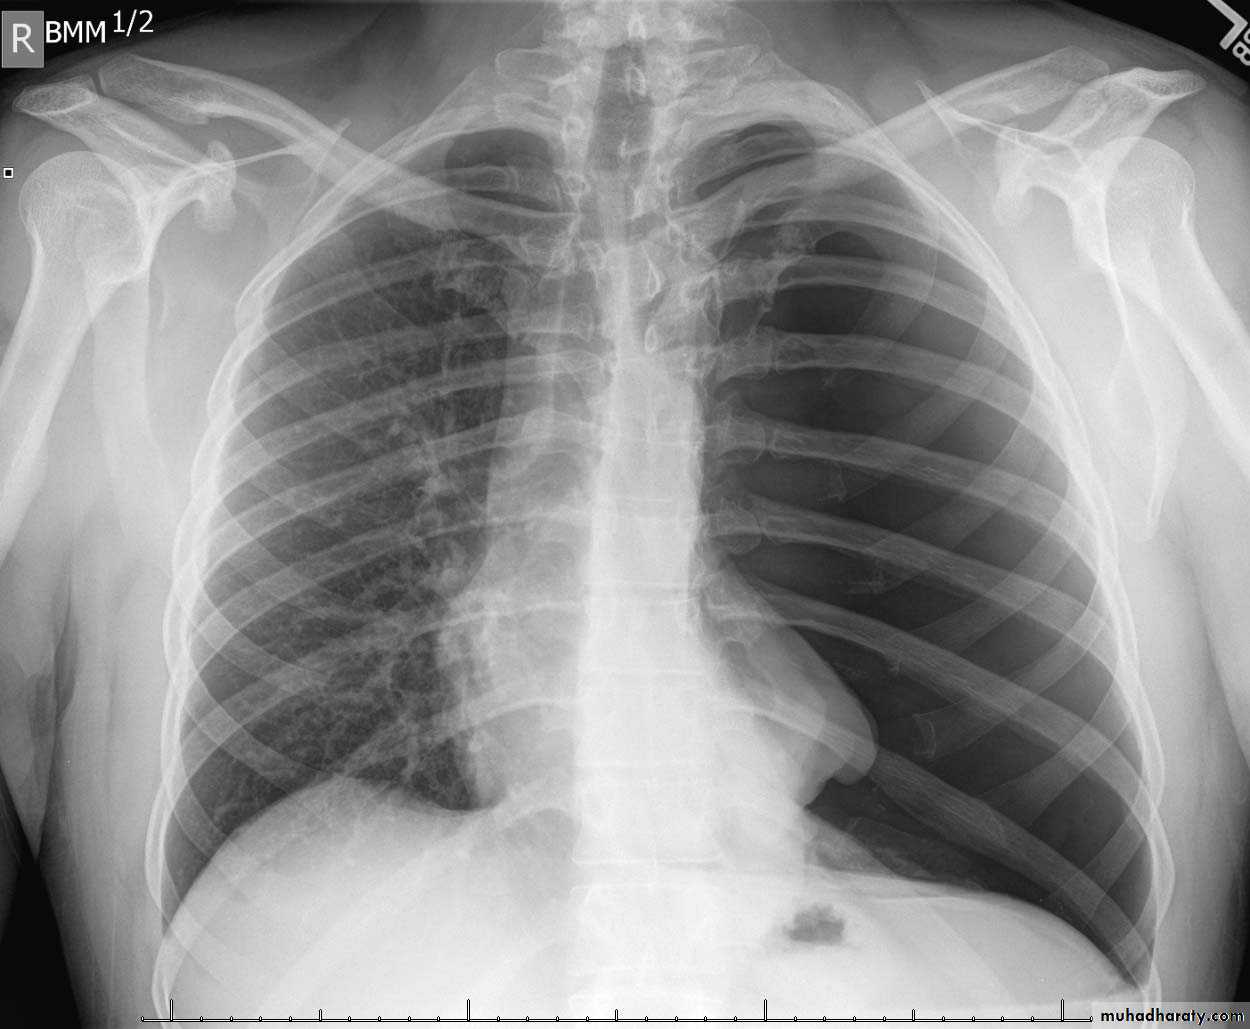

Bronchiactasis

Bronchiectasis refers to abnormal dilatation of the bronchial tree and is seen in a variety of clinical settings. CT is the most accurate modality for diagnosis. It is largely considered irreversibleCauses of bronchiactasias very important to consider

Plain radiograph

Chest x-rays are usually abnormal1. Tram-track opacities are seen in cylindrical bronchiectasis, and

2. air-fluid levels may be seen in cystic bronchiectasis.

Honey comb shadow

3.Overall there appears to be an increase in bronchovascular markings, and bronchi seen end on may appear as ring shadows .

4.Pulmonary vasculature appears ill-defined, thought to represent peri bronchovascular fibrosis .